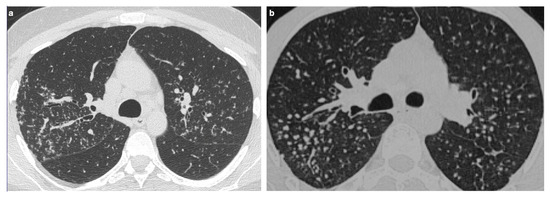

The Role of High-Resolution Lung Computed Tomography to Distinguish Between Fibrosing Hypersensitivity Pneumonitis and Usual Interstitial Pneumonia

by Dmitry A. Kuleshov, Svetlana Yu. Chikina, Galina V. Nekludova, Igor E. Tyurin and Sergey N. Avdeev

Background: Hypersensitivity pneumonitis (HP) is an interstitial lung disease (ILD) caused by repeated exposure to inhaled antigens in susceptible subjects. High-resolution computed tomography (HRCT) of the lungs is the leading diagnostic method for ILDs, but in some cases HRCT findings are not sufficient to distinguish HP and other ILDs, particularly, fibrotic HP (fHP) and usual interstitial pneumonia (UIP). Objective: The aim of this study was to develop HRCT criteria to diagnose fHP in patients with a UIP-like pattern. Methods: In this retrospective study, we analyzed HRCT scans of patients with fHP and a UIP-like pattern who underwent lung biopsy, and patients with idiopathic pulmonary fibrosis (IPF) and a UIP pattern in HRCT. Results: We included 51 patients with confirmed fHP and 24 patients with IPF/UIP in the analysis. IPF/UIP patients were older, were prevalently males, and did not have any systemic autoimmune diseases or risk factors for other ILDs. fHP patients were younger, with an equal number of males and females, and were more likely to be exposed to environmental antigens. HRCT abnormalities in the fHP group predominated in the lower lung areas or were diffuse in axial scans, whereas IPF/UIP patients mostly demonstrated a diffuse craniocaudal distribution and subpleural axial predominance. Centrilobular nodules and mosaic attenuation were present significantly more often in the fHP group; honeycombing, traction bronchiectasis, and emphysema prevailed in IPF/UIP patients. In the logistic regression analysis, patients with fHP and IPF/UIP differed in the presence of centrilobular nodules, honeycombing, and in both craniocaudal and axial distributions of HRCT abnormalities. In the ROC analysis, the combination of centrilobular nodules, honeycombing, and diffuse axial and craniocaudal distributions can predict the diagnosis of fHP (AUC, 0.953 ± 0.022; 95%CI, 0.910–0.995; p < 0.001). Mosaic attenuation and reticulation did not change the probability of fHP. Conclusions: The most significant HRCT features of fHP compared to the UIP pattern were centrilobular nodules, honeycombing, and a diffuse axial and craniocaudal distribution of abnormal findings. Reticulation, mosaic attenuation, and GGO do not increase the probability of fHP. Full article